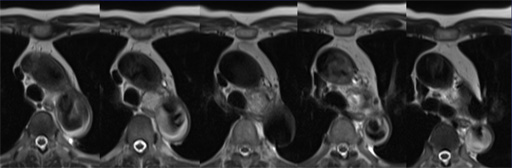

症例7 : 図12 DWI (b=500),ADC map